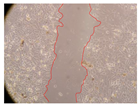

In the present study, the healing potential of 8 decoctions used in the preparation of ayahuasca was evaluated, using the wound scratch test. The evolution of the scratch created was monitored using microscopic images (Table 2) and the distance between the margins of the lesion was calculated (Table 3). Analysing the images that showed the evolution of the distance between the margins of the lesion and comparing them with the control samples, it was possible to verify that, in general, all the samples showed a great decrease in the lesion, and after 24 h of incubation, the samples of M. hostilis + P. harmala at 500 mg/L and P. viridis + B. caapi at 250 mg/L showed the best results. However, analysing the evolution of the distance calculated, only the sample of the commercial mixture at 250 mg/L after 2 h of incubation did not show a significant decrease. All other samples at different evaluation times, as well as the commercial mixture at 250 mg/L at the other times (8 h, 12 h and 24 h) showed a significant decrease in lesion margins compared to the control.

Table 2.

Microscopic images obtained from the scratch wound-healing assay with the samples of ayahuasca (magnification: 100×). The margins of the scratch appear in red.

These results are indicative of the healing activity of the samples tested. It is possible to observe in the images of Table 2 the migration of the fibroblasts incubated with the samples at different concentrations. In these images, it was possible to verify that the lesions closed over time, which was in accordance with the distance calculated between the margins of the lesion. As far as we know, to date there are no studies where the healing potential of ayahuasca has been evaluated, and it is not possible to compare the results now obtained. However, these results can be explained by the antioxidant and anti-inflammatory activity previously studied in these samples [], since it is reported that antioxidant activity and healing properties coexist in plant extracts []. Wound healing consists of the reconstruction of the lesion, involving several interactions between epithelial cells, growth factors, cytokines and chemokines. It has been reported that natural products, namely plant extracts, are involved in the proliferation of fibroblasts and keratinocytes, and may contain cell adhesion molecules, growth factors and cell signalling molecules, which can promote lesion reconstruction []. This in vitro assay, which, unlike conventional assays used to determine the healing properties of plant material, was non-invasive, allowed the screening of several samples with antibacterial, anti-inflammatory and antioxidant properties, which are important in wound healing [,].